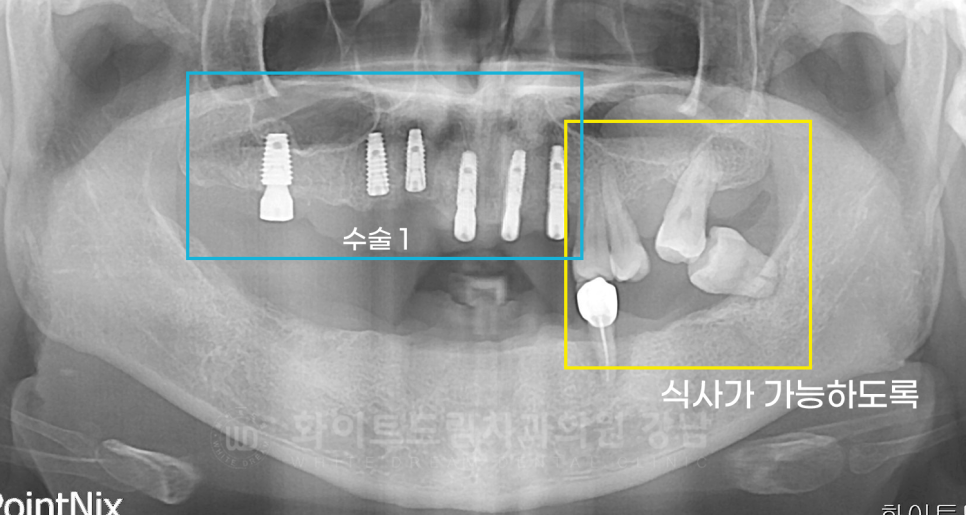

임플란트는 총 3회에 걸쳐 부분적으로 진행했습니다.

수술 1) 10번대 수술 (20.04.04)

16, 14, 13, 11, 21, 23, 24 번 임플란트를 식립했고,

이중 16번은 상악동 거상술 (crestal)을 이용하여 부족한 잇몸뼈를 보강했습니다.

수술 2) 20번, 30번대 수술 (20.04.18)

24, 26, 34, 36번 임플란트 식립과 lateral 방식의 상악동 거상술 수술을 진행했습니다.

수술 1차에서 16번 치아도 상악동 거상술을 진행했는데, 술식이 다르죠?

16번은 crestal 방식을 이용했고

24, 26번은 laterla 방식을 이용했습니다.

치료 후 x-ray를 보면 식립된 뼈의 양이 다른 것이 한눈에 보이실 겁니다.